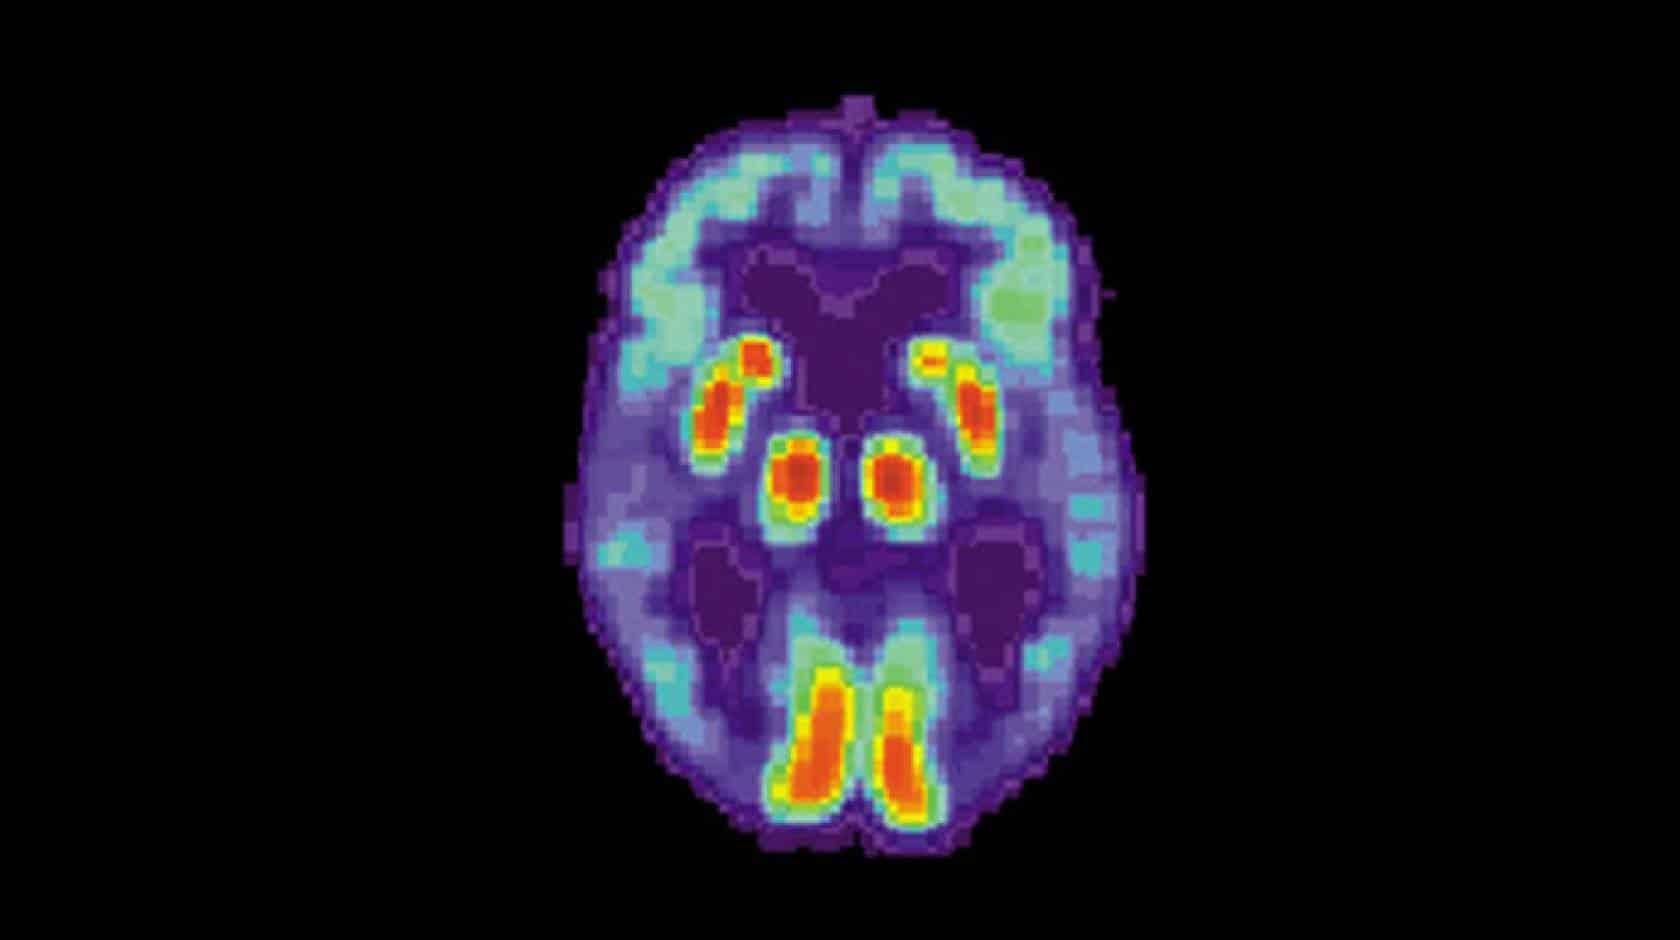

ПЭТ-сканирование мозга пациента с болезнью Альцгеймера. / National Institute on Aging

Сахар помог защититься от болезни Альцгеймера   Медицина

До сих пор считалось, что гликоген — полисахарид из остатков глюкозы — накапливается в нейронах у пациентов с деменцией вследствие болезни. Однако результаты нового исследования показали, что расщепление гликогена активирует …